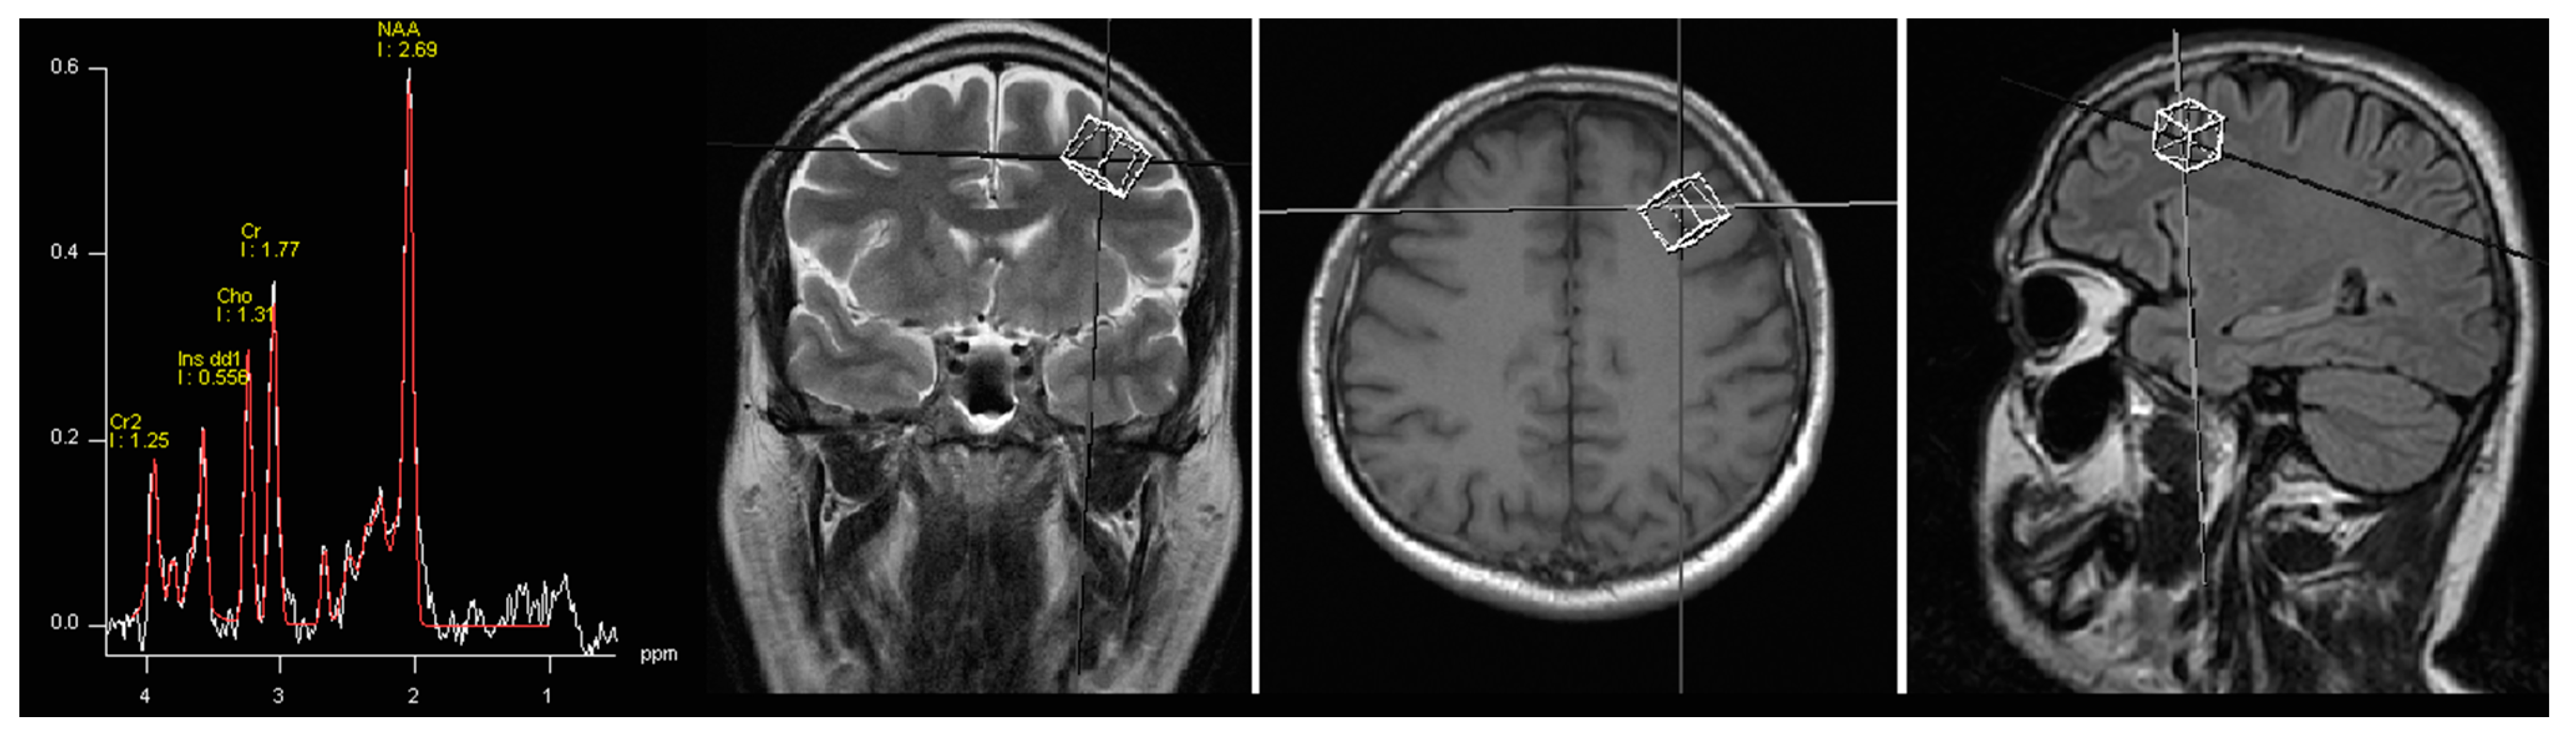

3.1. Spectroscopy